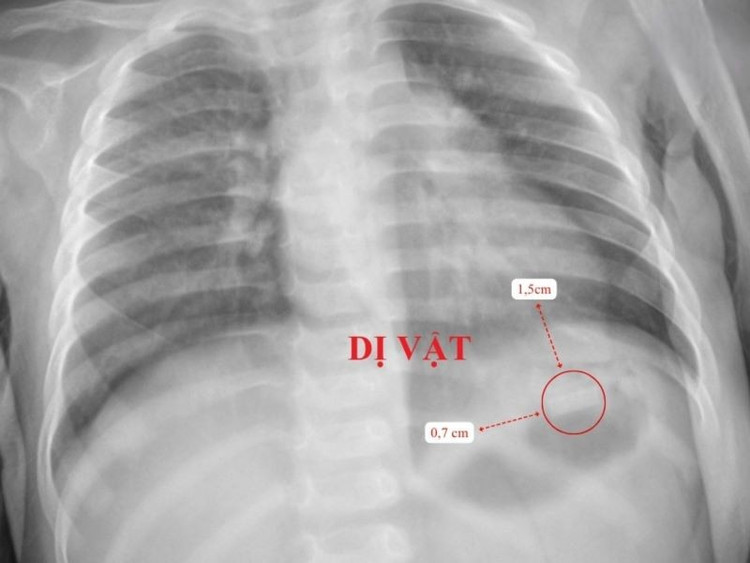

Kết quả thăm khám lâm sàng và cận lâm sàng cho thấy một dị vật kim loại hình chữ nhật kích thước 1,5x0,7cm, có góc nhọn, mỏng và sắc như lưỡi dao nằm tại vùng hạ sườn trái, vị trí bóng hơi dạ dày của bé T.

Vị trí dị vật trên phim chụp X-quang - Ảnh BVCC